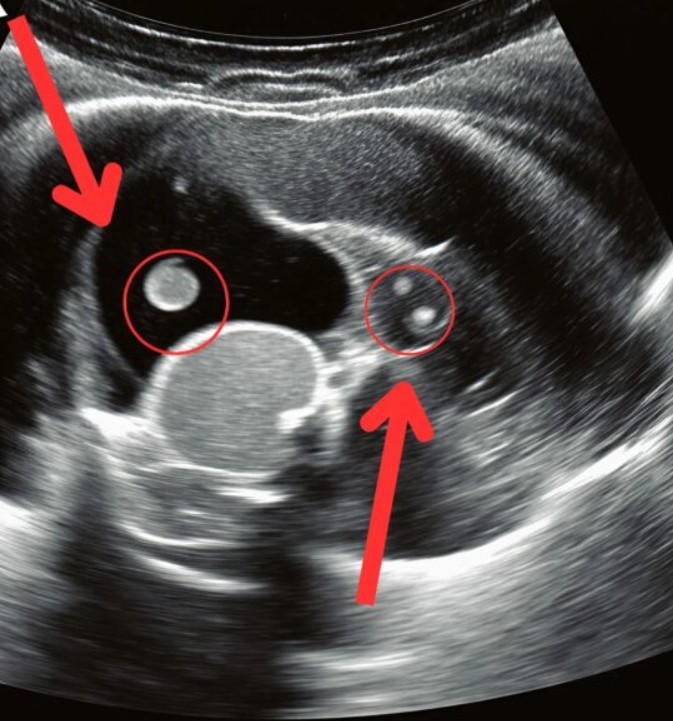

In de gangen van de spoedeisende hulp leek de tijd stil te staan. Terwijl mijn dochter op de brancard kronkelde van de pijn, wachtten we onder bezorgde blikken van de dokters op de resultaten van de echo. Eindelijk kwam de arts naar ons toe en sprak de woorden die geen ouder ooit wil horen: “Een spoedoperatie is nodig.” Wat we dachten dat rugpijn door haar tas kwam, bleek stilletjes een niersteen te zijn die gegroeid was. De steen was verschoven en in de urineleider terechtgekomen, waardoor hevige pijn en een levensgevaarlijke situatie ontstonden.